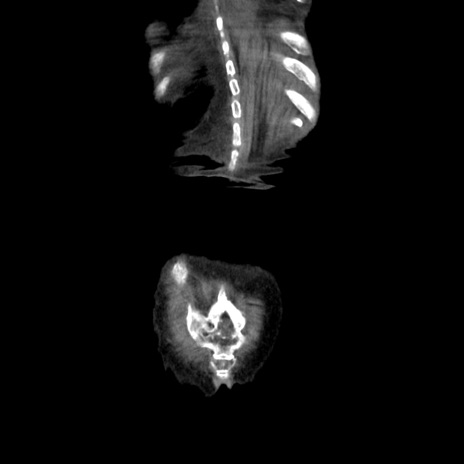

横断像

【症例】80歳代女性

【主訴】嘔吐、腹痛

【現病歴】数時間前より嘔吐あり。心窩部痛出現し、徐々に右下腹痛あり。その後も数回嘔吐あり救急搬送となる。

【既往歴】左大腿骨頚部骨折手術

【身体所見】腹部は膨隆しているが軟らかく圧痛なし。腸雑音はやや亢進。

【データ】WBC 12000、CRP 19.05